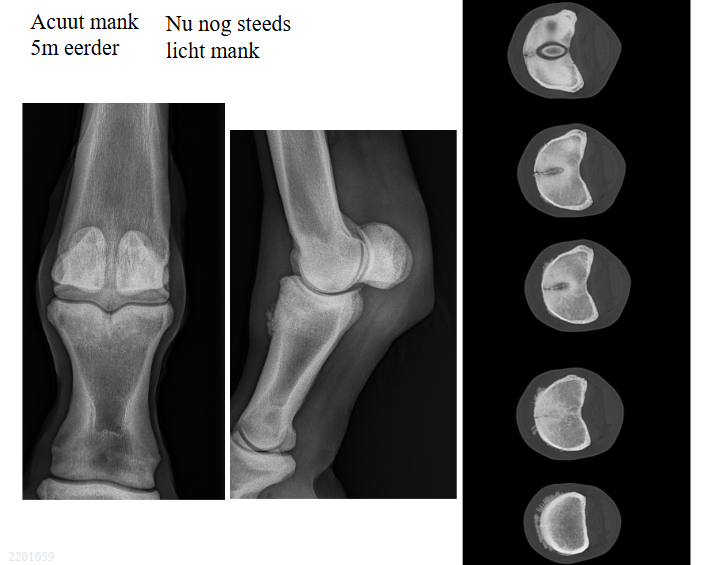

Intra- of extra-articulair?

Intra-articulair: niet in het femoro-tibiale gewricht, wel in het femoro-patellaire gewricht

Configuratie?

totale fractuur

Fragmentatie?

Verbrijzeld